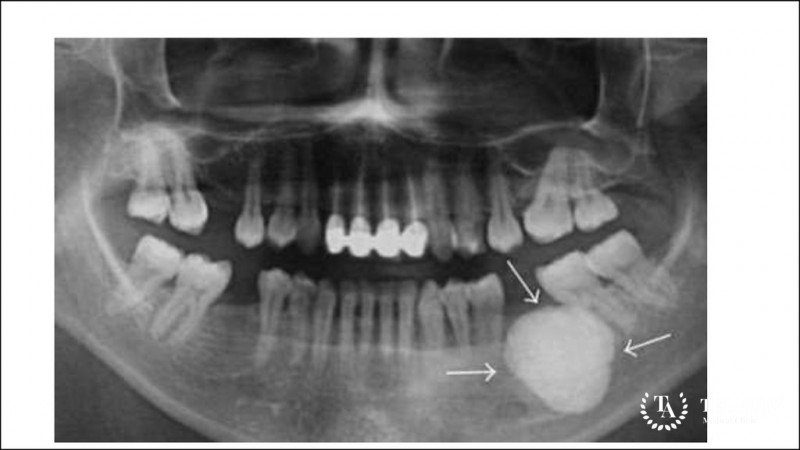

Диагноз остеома ставится на основании осмотра и опроса больного. Однако для подтверждения диагноза может быть назначена рентгенография. Поскольку опухоль имеет небольшие размеры, данный диагностический метод не всегда является эффективным. С учетом особенностей расположения неоплазии, наиболее информативным методом диагностики является компьютерная томография.